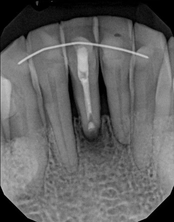

Apicoectomy:

Before, the failed root canal

Immediately after the microsuregery

3-months after shows complete healingThe patient was told by a specialist that the root canal failed, the only option was extraction and an implant. She did not want to do that; she wanted to keep her tooth, after all, it is her front tooth. She found us. We performed an apical microsurgery with the laser. The tooth was saved and is still functioning. This is a poor area for an implant, so much better to save the tooth.